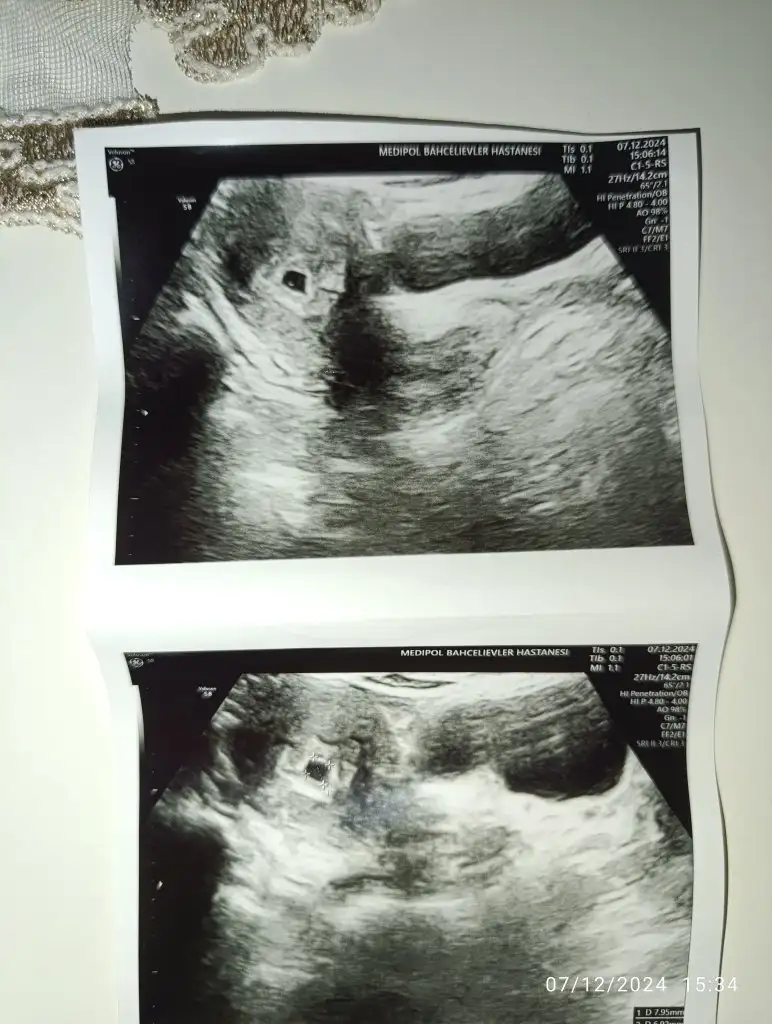

MaşallahKızlar çok şükür kese büyümüş yolk saç da görüldü bugün![]()

Oh gözün aydın canım hep böyle güzel haberlerle çık doktor odasından inşallahKizlarrrrrkese göründü şükürler olsun Rabbime.haftası ile uyumlu dedi.heyecandan hicbirsey soramadım mal gibi baktım doktorun suratına

Canım evet miniminnak bir nokta var o bebek olacakCanimmmm çok sağolun valla öyle stresli gittim ki rabbim gulerek çıkardı.Allah kimseyi umdugundan geri koymasındoktor yolk kese demedi ama görüntü atıyorum size bakinsana orada bir nokta var yolk mu?Desteğiniz duanız için çok ama çok teşekkür ederim Rabbim iki cihanda güldürsün yüzünüzü